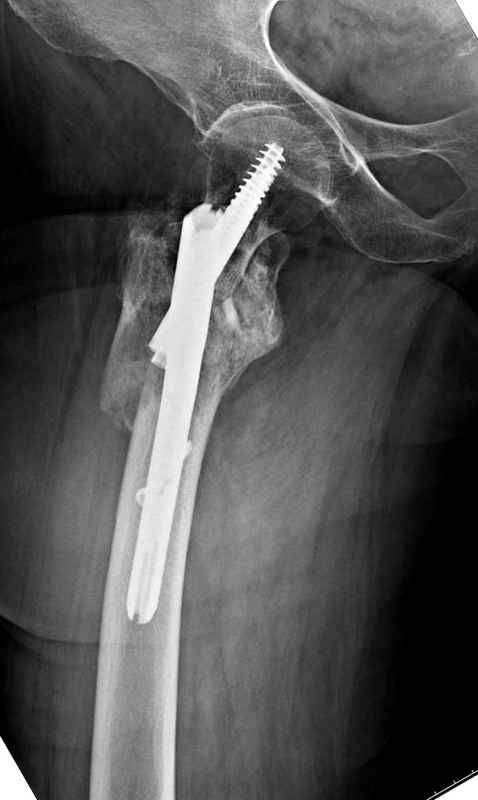

Re: Чрезвертельный перелом бедра

послал Djoldas Kuldjanov 25 Август 2009, 22:19

Здесь 83 года, травма в результате падения